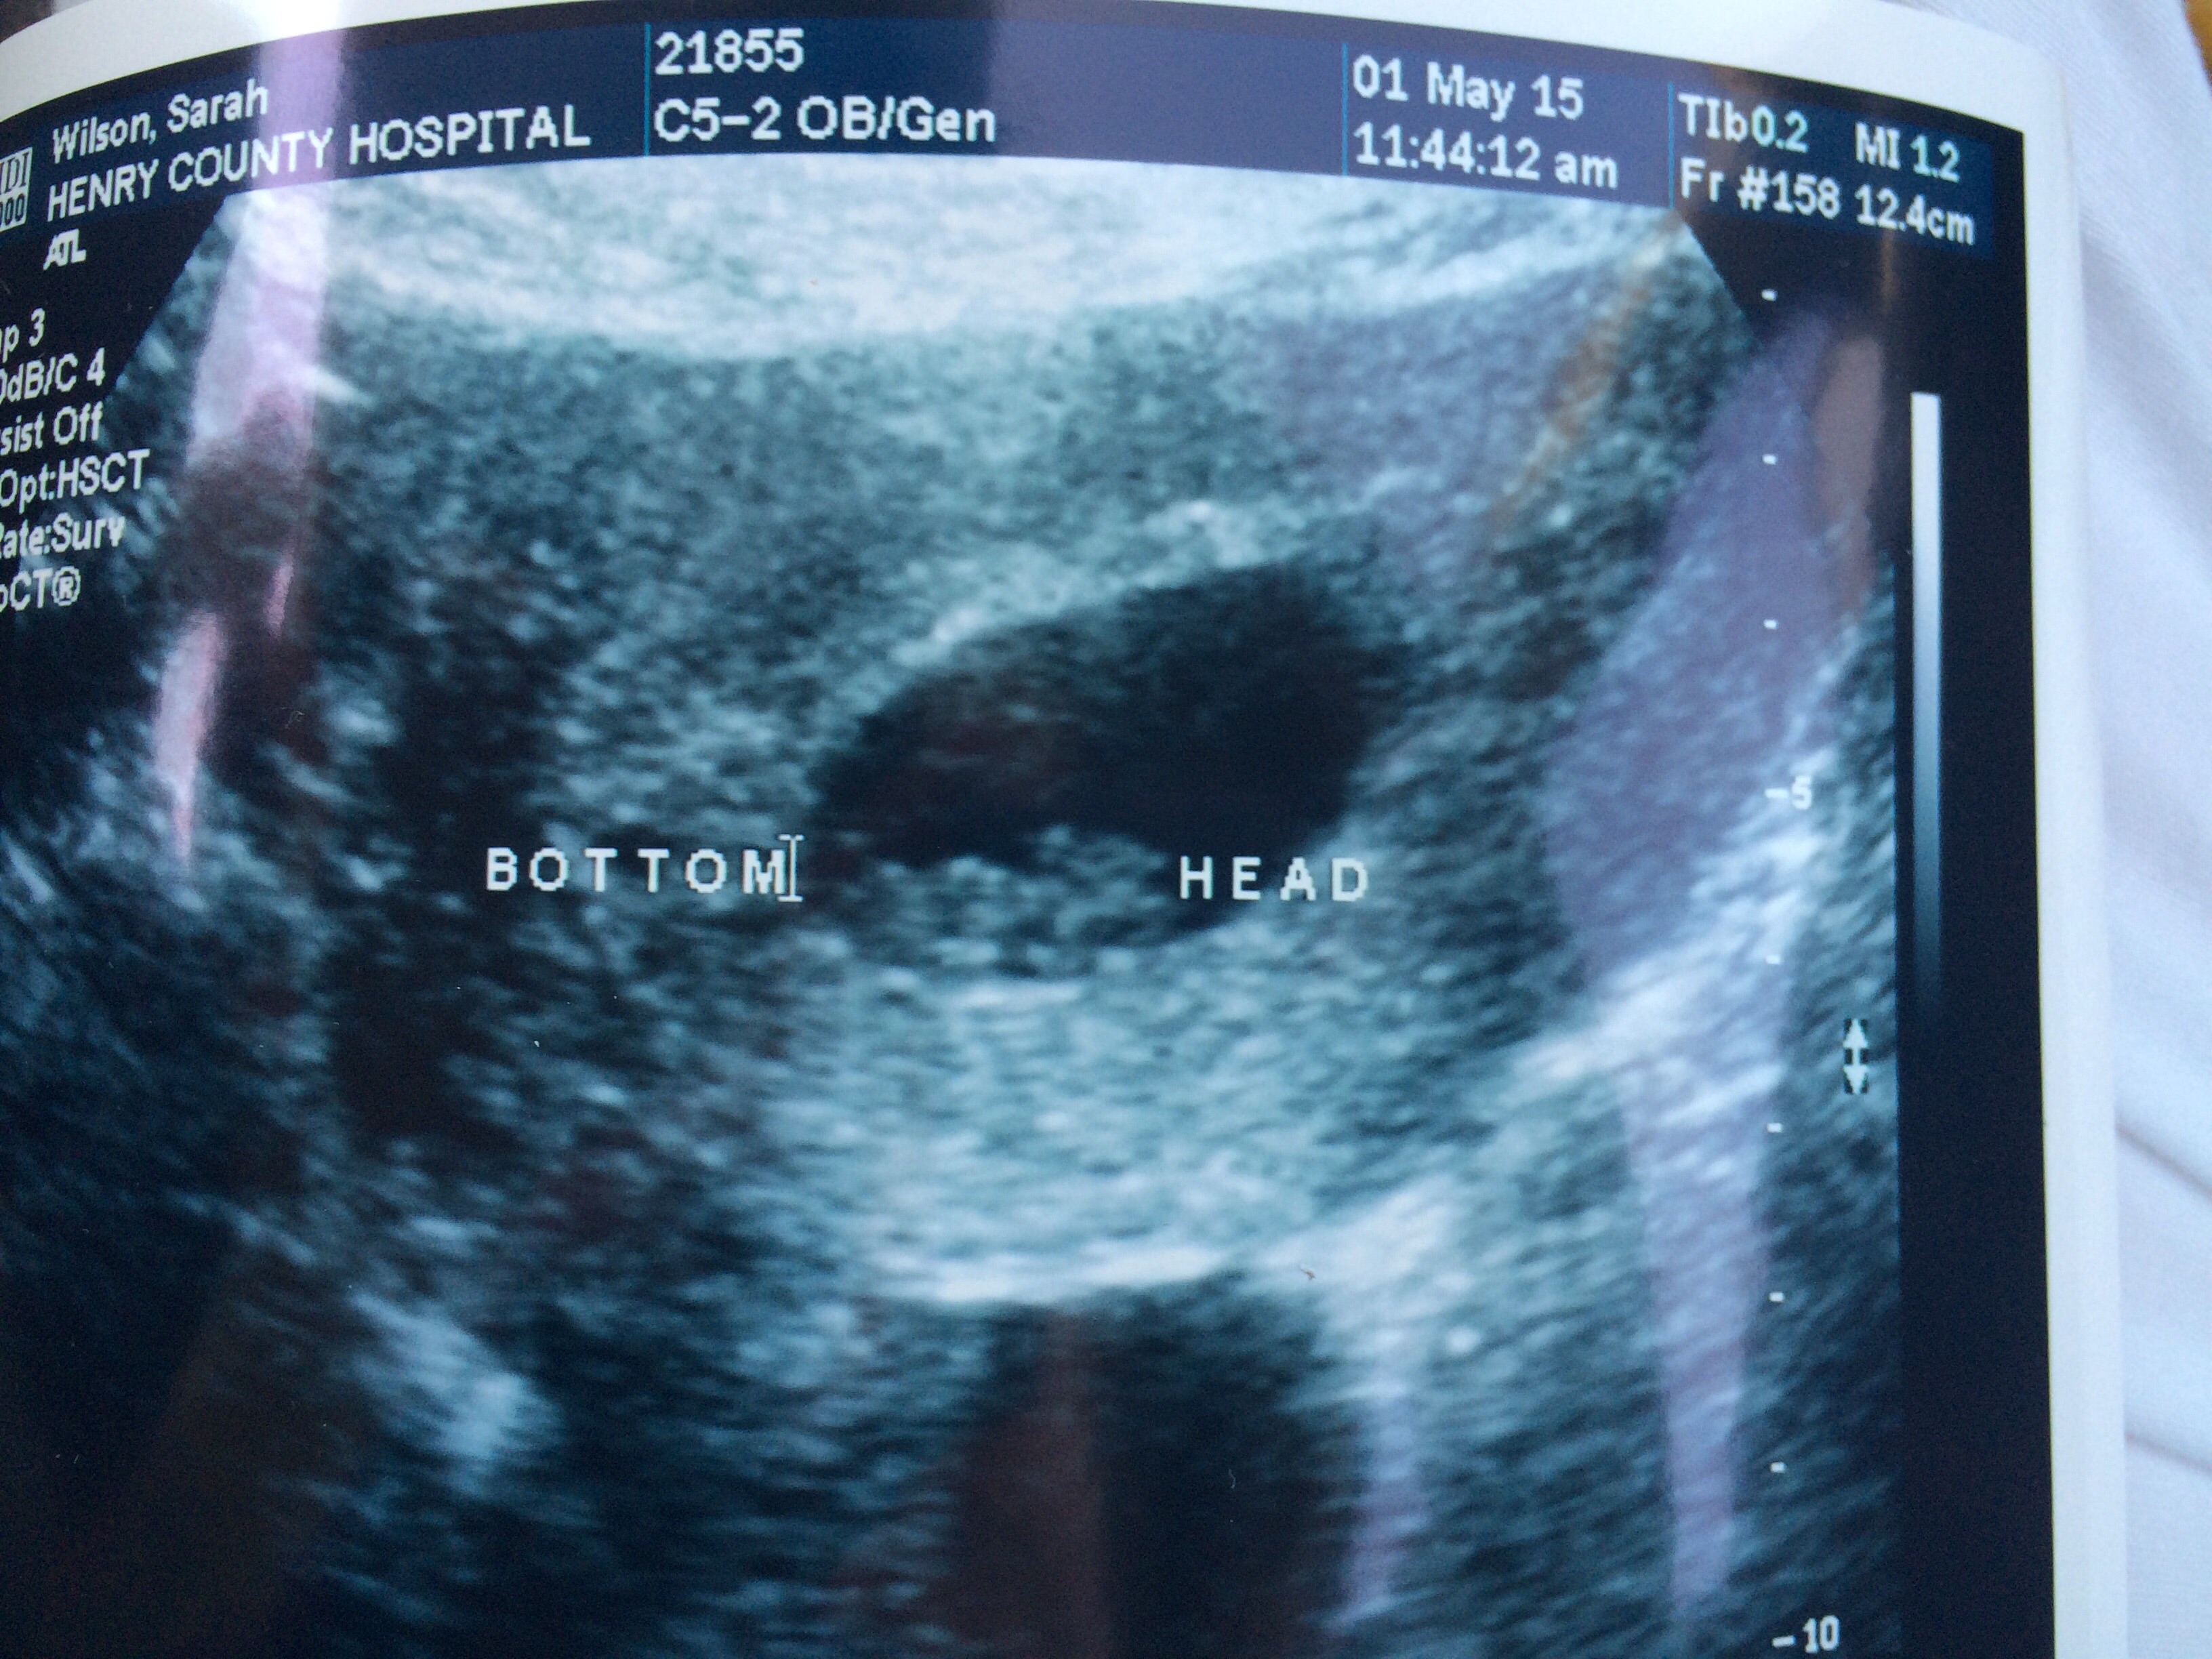

10w1d they zoomed in so I could see baby better, love my little human.. Still think the best was when my cousin goes congratulations your having a human